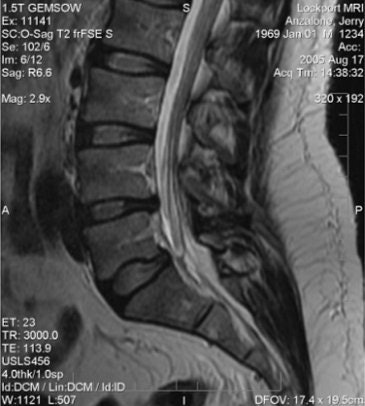

![]() |

| Above, nonaxial-loaded images. Below, axial-loaded images. Increase in stenosis at L4 level by 2.0 mm and left L4 spinal nerve root with axial loading. All images courtesy of Dr. Gerald Anzalone. |